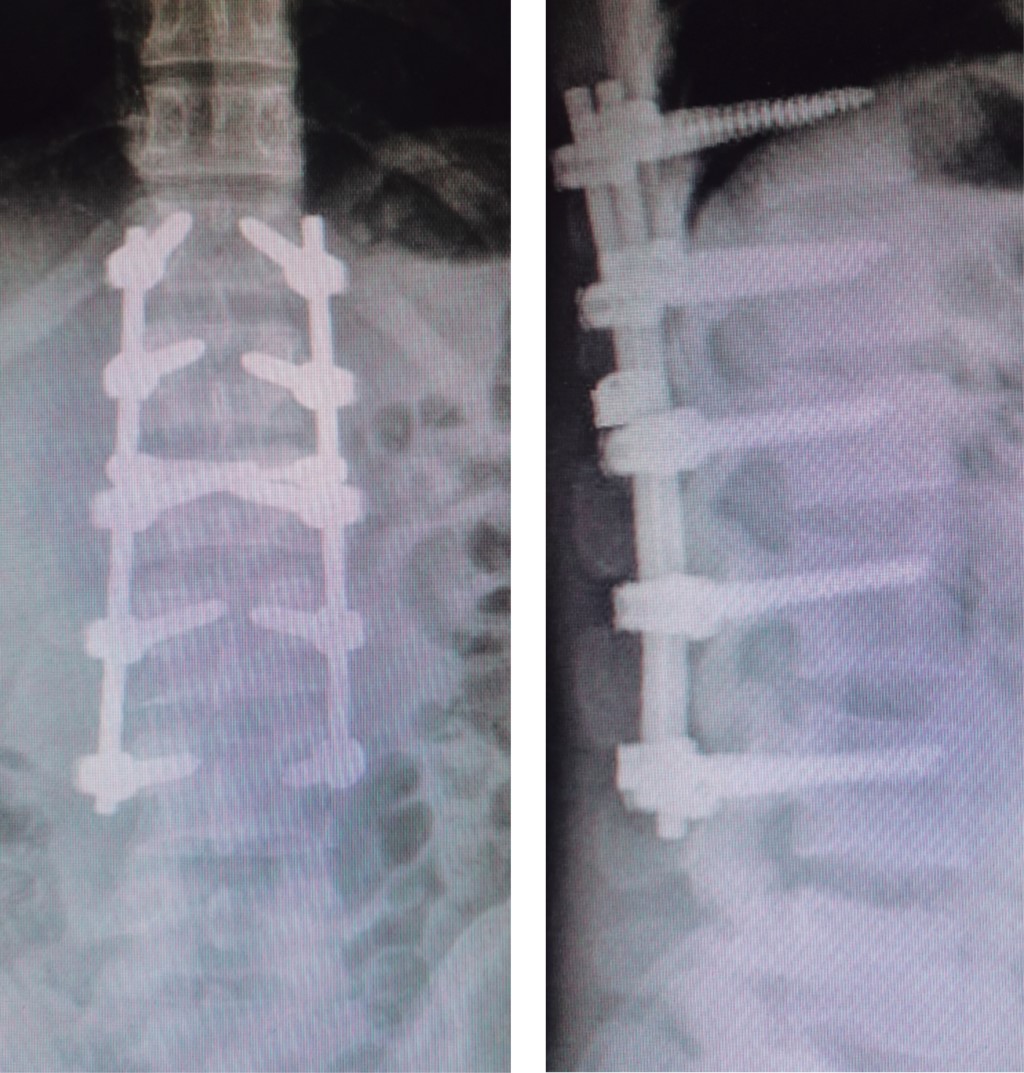

Figure 2